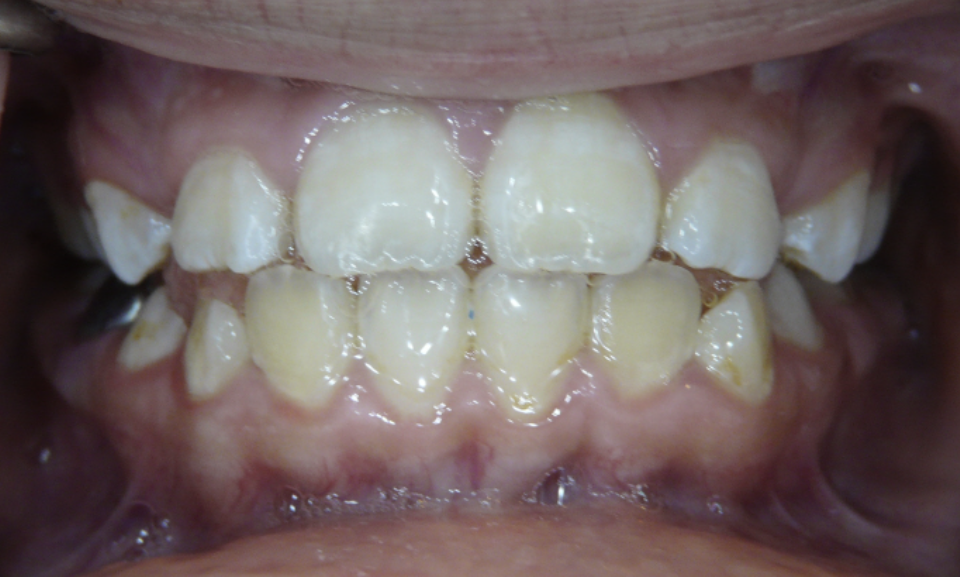

Openbite

Front teeth do not meet when teeth are closed.